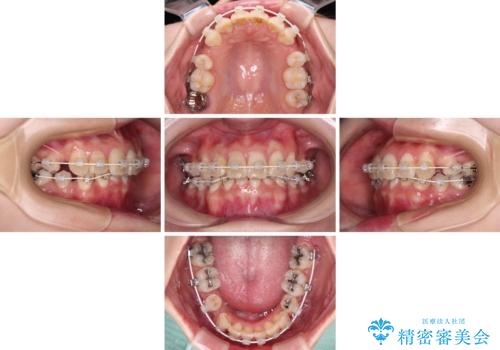

デコボコと深い咬み合わせ ワイヤー装置での抜歯矯正

- 内側に倒れ込んだ歯や下の前歯が隠れてしまうほどの咬み合わせを改善したいとのことで来院された患者様です。

下顎の叢生を解消するために抜歯が必要であり、奥歯の咬み合わせや口元の印象から、上顎も同様に抜歯と判断し、上下左右の第1小臼歯4本抜歯してワイヤー装置にて矯正治療を行うこととしました。

咬み合わせが深く、そのままでは上顎の抜歯スペースが閉じきらない可能性があったため、治療初期から深い咬み合わせを改善させるように試みました。

実際にはなかなか改善されず、当初予定よりも治療期間がやや長期化してしまいました。